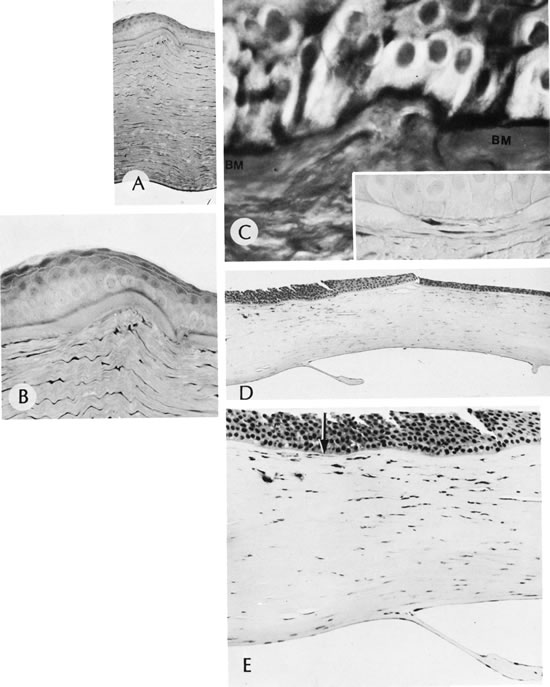

SCLEROCORNEA

Sclerocornea is a totally opacified cornea that shows clinical and histologic features of sclera. The condition often is bilateral. Superficial or deep vascularization of the tissue may occur. Associated clinical conditions include nystagmus, strabismus, aniridia, cornea plana, macular hypoplasia, horizontally oval cornea, and glaucoma.76 As described in Mieten's syndrome, sclerocornea may present with congenital cerebral dysfunction, deafness, cryptorchidism, pulmonary disease, brachycephaly, and defects of the face, ears, and skin. Sclerocornea may be inherited in an autosomal dominant pattern. It may result from intrauterine inflammation and other nonspecific causes.

Histologically, increased numbers of collagen fibrils with a variable collagen diameter occur in the normal corneal stroma. Descemet's membrane appears thin.77,78 Bowman's membrane may be absent.79

Sclerocornea has been associated with an interstitial deletion of the short arm of chromosome 6(46XY del[6 [p22 p24])80 and a microdeletion of Xp22.3.81,82 Recent evidence supports linkage to mutations in the distal arm of chromosome 6.80